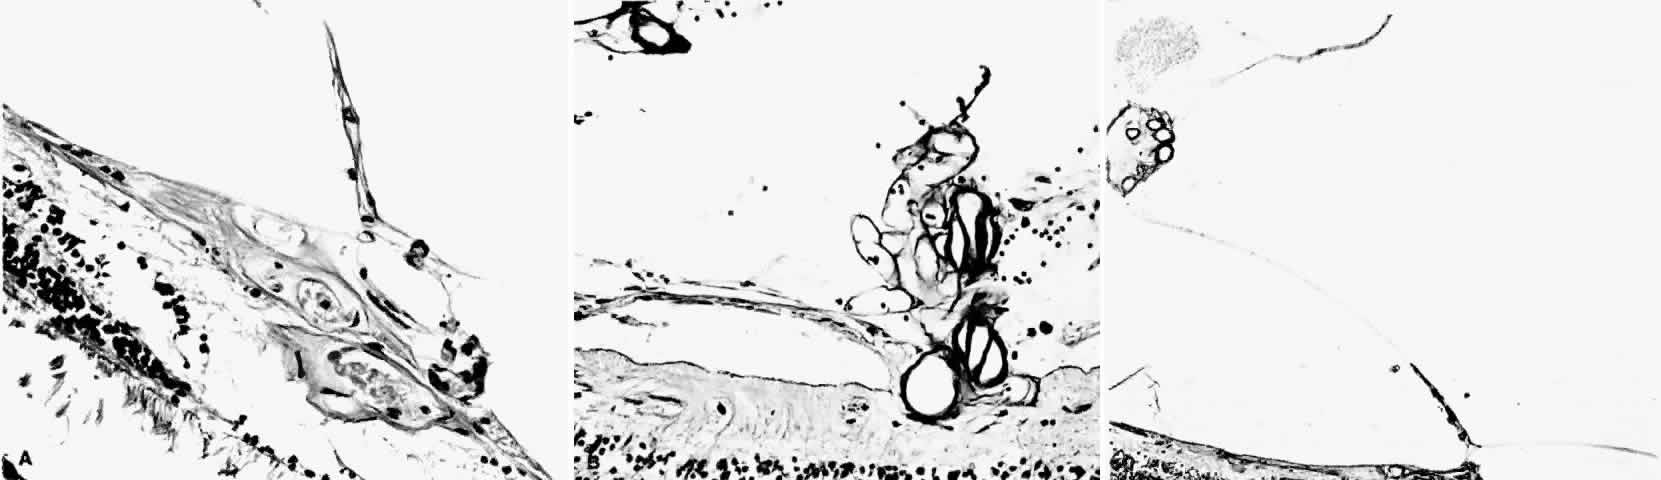

Histologic and trypsin digest studies support the theory of a sudden occlusion of the precapillary arteriolar circulation followed by degeneration of the occluded vessels and the distal nonperfused retina. The presence of focal areas of small vessel degeneration and vascular beading (but not typical retinal microaneurysms) also have been confirmed.132

STAGE III: PRERETINAL NEOVASCULARIZATION (PROLIFERATIVE SICKLE RETINOPATHY). “Sea fan”-shaped neovascularization typically develops on the venular side of an arteriolar-venular anastomosis, mimicking the normal development of retinal capillaries (Fig. 24).125 A lowered oxygen tension and angiogenic factors released on the venular side may be the stimulus for neovascular growth.125,126 In most instances, the direction of growth is toward the ora serrata, from the perfused retina toward the nonperfused retina. Presumably, this represents an abortive attempt to revascularize the nonperfused retina, initiated by vasoproliferative factors.

Fig. 24. A. Photograph of the peripheral retina, demonstrating several small fibroglial membranes. B. Fluorescein angiogram corresponding to A, showing multiple arteriolar-venular anastomoses with early sea fan formation. C. Photograph of the same area 2 years later demonstrates more fibroglial membranes. D. Fluorescein angiogram corresponding to C shows new sea fans caused by an arteriolar-venular anastomosis (curved arrow). Large arrow (A through D) identifies corresponding arteriolar bifurcation.

PSR is associated with the severe vision-threatening sequelae of sickle cell disease: vitreous hemorrhage (stage IV) and retinal detachment (stage V). These stages are believed to result from transudation of blood components into the vitreous through the incompetent neovascular tissue (Fig. 28). Vitreous fluorophotometry has quantified the leakage from the peripheral neovascularization.134 This leads to premature syneresis and collapse of the vitreous, inducing tractional forces on the retina that lead to vitreous hemorrhage, retinal tears, and tractional and rhegmatogenous retinal detachment. In rare cases, an exudative detachment may occur.

Fig. 28. A. Cross-section of retina shows vitreous adhesions to flat neovascular tissue (stage III proliferative sickle cell retinopathy [PSR]).Fig. 28 (continued).B. Cross-section of retina reveals large clump of neovascular tissue (stage III PSR) protruding from surface of retina into vitreous. C. Cross-section of retina and vitreous. Note large cluster of intravitreous neovascular tissue adherent to vitreous traction bands. (Romayananda N, Goldberg MF, Green WR: Histopathology of sickle cell retinopathy. Trans Am Acad Ophthalmol Otolaryngol 77:652, 1973.)